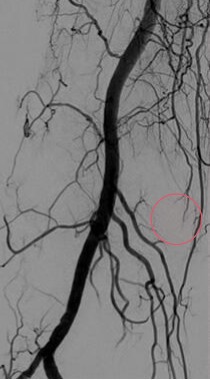

Après cartographie 2D/3D des structures artérielles, un cathéter (petit tuyau creux) est guidé, sous contrôle radiologique permanent jusqu’aux artères géniculées. Un agent embolisant est alors injecté dans les artères pathologiques pour en interrompre le flux sanguin, permettant ainsi de contrôler l’hypervascularisation et l’inflammation et donc de stopper le cercle vicieux à l’origine des douleurs et de la progression de l’arthrose.

- Artériographie diagnostique : Un cathéter fin est inséré dans l’artère fémorale (ou parfois) et guidé jusqu’aux artères géniculées du genou douloureux. Cette étape est réalisée avec précision et en temps réel sous contrôle radiologique. Une cartographie artérielle est réalisée afin de bien comprendre l’anatomie vasculaire et de visualiser les zones cibles présentant une hypervascularisation dans la zone douloureuse. L’objectif est ensuite d’atteindre les artères responsables avec le matériel adapté.

- Injection de l’agent embolisant : Une fois le cathéter positionné correctement au sein des artères géniculées, l’agent embolisant est injecté prudemment dans les vaisseaux sanguins concernés sous contrôle radiologique permanent. Cet agent bloque progressivement le flux sanguin vers la zone hypervascularisée ce qui permet de stopper l’inflammation.

- Contrôle post-procédure : Une fois l’embolisation réalisée, une angiographie de contrôle est effectuée pour vérifier que le saignement est bien stoppé et que l’embolisation a été efficace. On vérifie aussi de manière systématique qu’il n’y ait pas d’anastomoses responsable d’une reprise du saignement par des voies détournées. Le patient est ensuite surveillé pendant quelques heures pour détecter d’éventuelles complications.